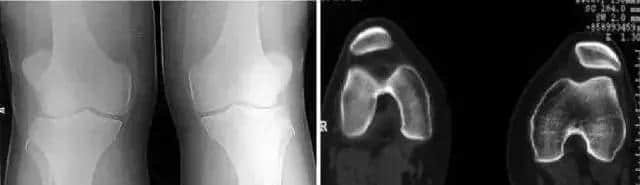

5 分裂 (二分)髕骨

常見(jiàn)于兒童,多雙側(cè)性。 一般認(rèn)為是正常骨化的變異,可在十幾歲時(shí)融合。癥狀:運(yùn)動(dòng)時(shí)疼痛或運(yùn)動(dòng)后疼痛,膝關(guān)節(jié)屈曲時(shí)疼痛、下跪時(shí)疼痛,上下樓梯時(shí)疼痛,行走時(shí)疼痛,受冷時(shí)疼痛。

分裂部扣擊痛:可誘發(fā)有癥狀的分裂髕骨的疼痛,無(wú)癥狀者陰性。分裂骨片局部骨性隆起。 股四頭肌萎縮, 髕骨摩擦音,大多無(wú)關(guān)節(jié)積液、跛行和關(guān)節(jié)活動(dòng)度受限。有時(shí)需與骨折鑒別。